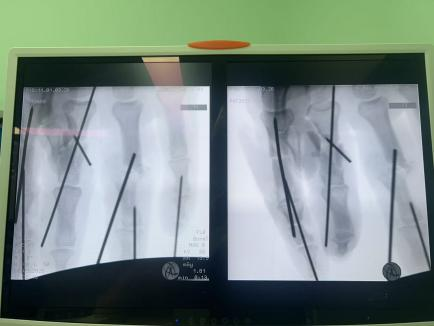

血管細(xì)如發(fā)絲:手指的動(dòng)靜脈直徑僅0.3-0.8毫米,醫(yī)生需要在顯微鏡下用比頭發(fā)絲還細(xì)的縫線進(jìn)行吻合;

多指同時(shí)再植:余女士食指、中指、無(wú)名指三指離斷,需同時(shí)重建血運(yùn),給手術(shù)醫(yī)師的精力和體力帶來(lái)極大考驗(yàn);

小拇指皮瓣修復(fù):小拇指軟組織缺損嚴(yán)重,醫(yī)生將精心設(shè)計(jì)皮瓣覆蓋創(chuàng)面,避免術(shù)后壞死;

骨折內(nèi)固定+肌腱神經(jīng)修復(fù):不僅要讓手指“活”,更要讓手指“能用”。

面對(duì)這些困難,許攀峰團(tuán)隊(duì)沒(méi)有卻步,沉著應(yīng)戰(zhàn)。他們先是為骨折的手指進(jìn)行精準(zhǔn)內(nèi)固定,重建骨骼支撐;隨后,在顯微鏡下,一根根尋找斷裂的血管、神經(jīng)和肌腱——清創(chuàng)、修剪、吻合、通血……每一步都如履薄冰,每一次打結(jié)都需屏息凝神,手術(shù)室內(nèi),寂靜無(wú)聲,只有時(shí)鐘的滴答聲在空氣中回蕩,仿佛在為這場(chǎng)生命的接力默默計(jì)時(shí)。

1小時(shí)、2小時(shí)、3小時(shí)…… 時(shí)間在寂靜中流逝,顯微鏡下,一雙雙手在無(wú)聲地忙碌著,他們的動(dòng)作嫻熟而精準(zhǔn),如同在跳一場(chǎng)無(wú)聲的生命舞蹈。終于,將近5個(gè)小時(shí)后,最后一針縫線完成。松開(kāi)止血鉗,所有再植的手指瞬間恢復(fù)紅潤(rùn),指腹飽滿,毛細(xì)血管反應(yīng)靈敏——手術(shù)成功了!這一刻,手術(shù)室內(nèi)壓抑的氣氛瞬間被打破,許攀峰團(tuán)隊(duì)成員們臉上露出了欣慰的笑容。